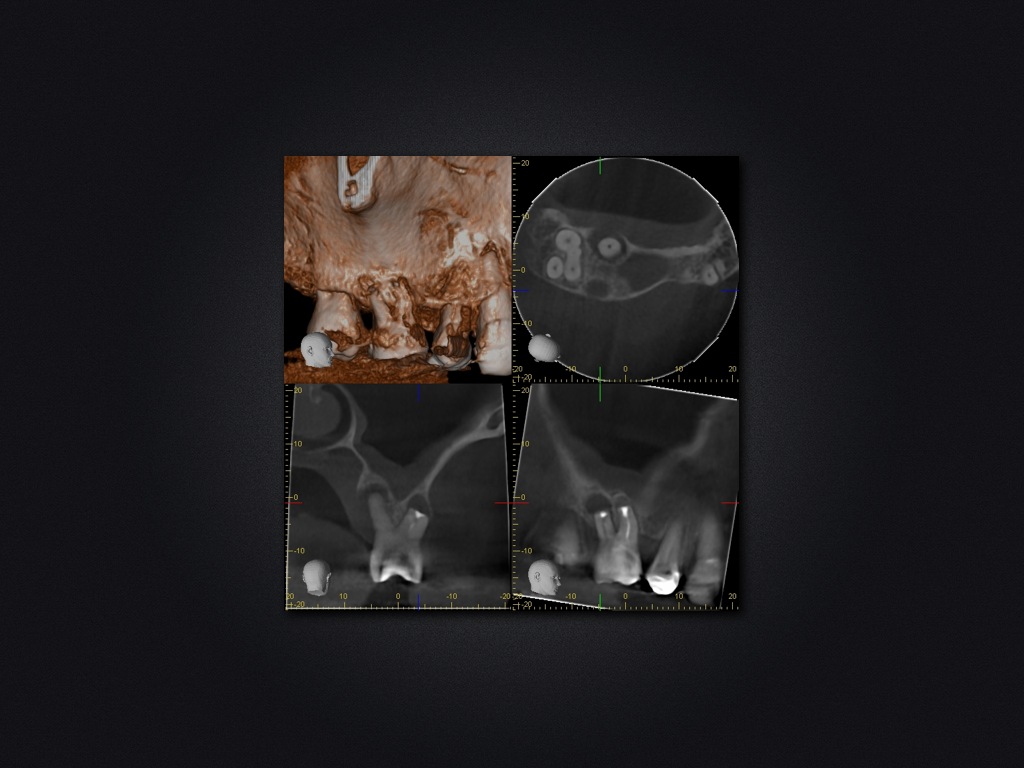

16D.005

Saving Hopeless Teeth (XXX)